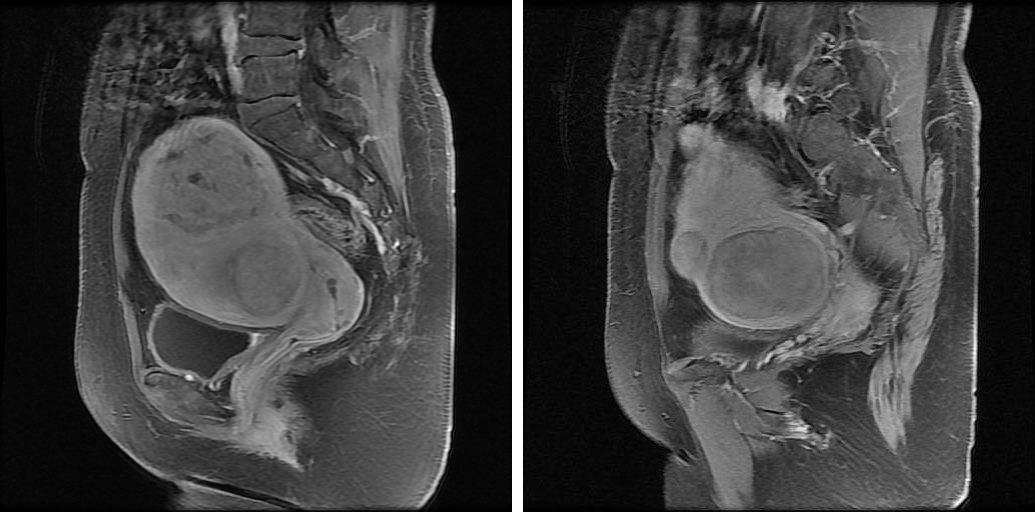

图片

* MRI显示:MRI显示:子宫形态不规则,大小约10.7×8.9×6.9cm,浆膜下、肌层及粘膜下多发(10枚左右)类圆形结节、肿块影,大部分呈等T1T2信号影,最大者位于子宫体左侧部,大小约6.3×4.2cm,增强扫描未见明显强化。相邻宫腔受压变形。颈部多发小囊样异常信号,大者直径约0.6cm,无明显强化。